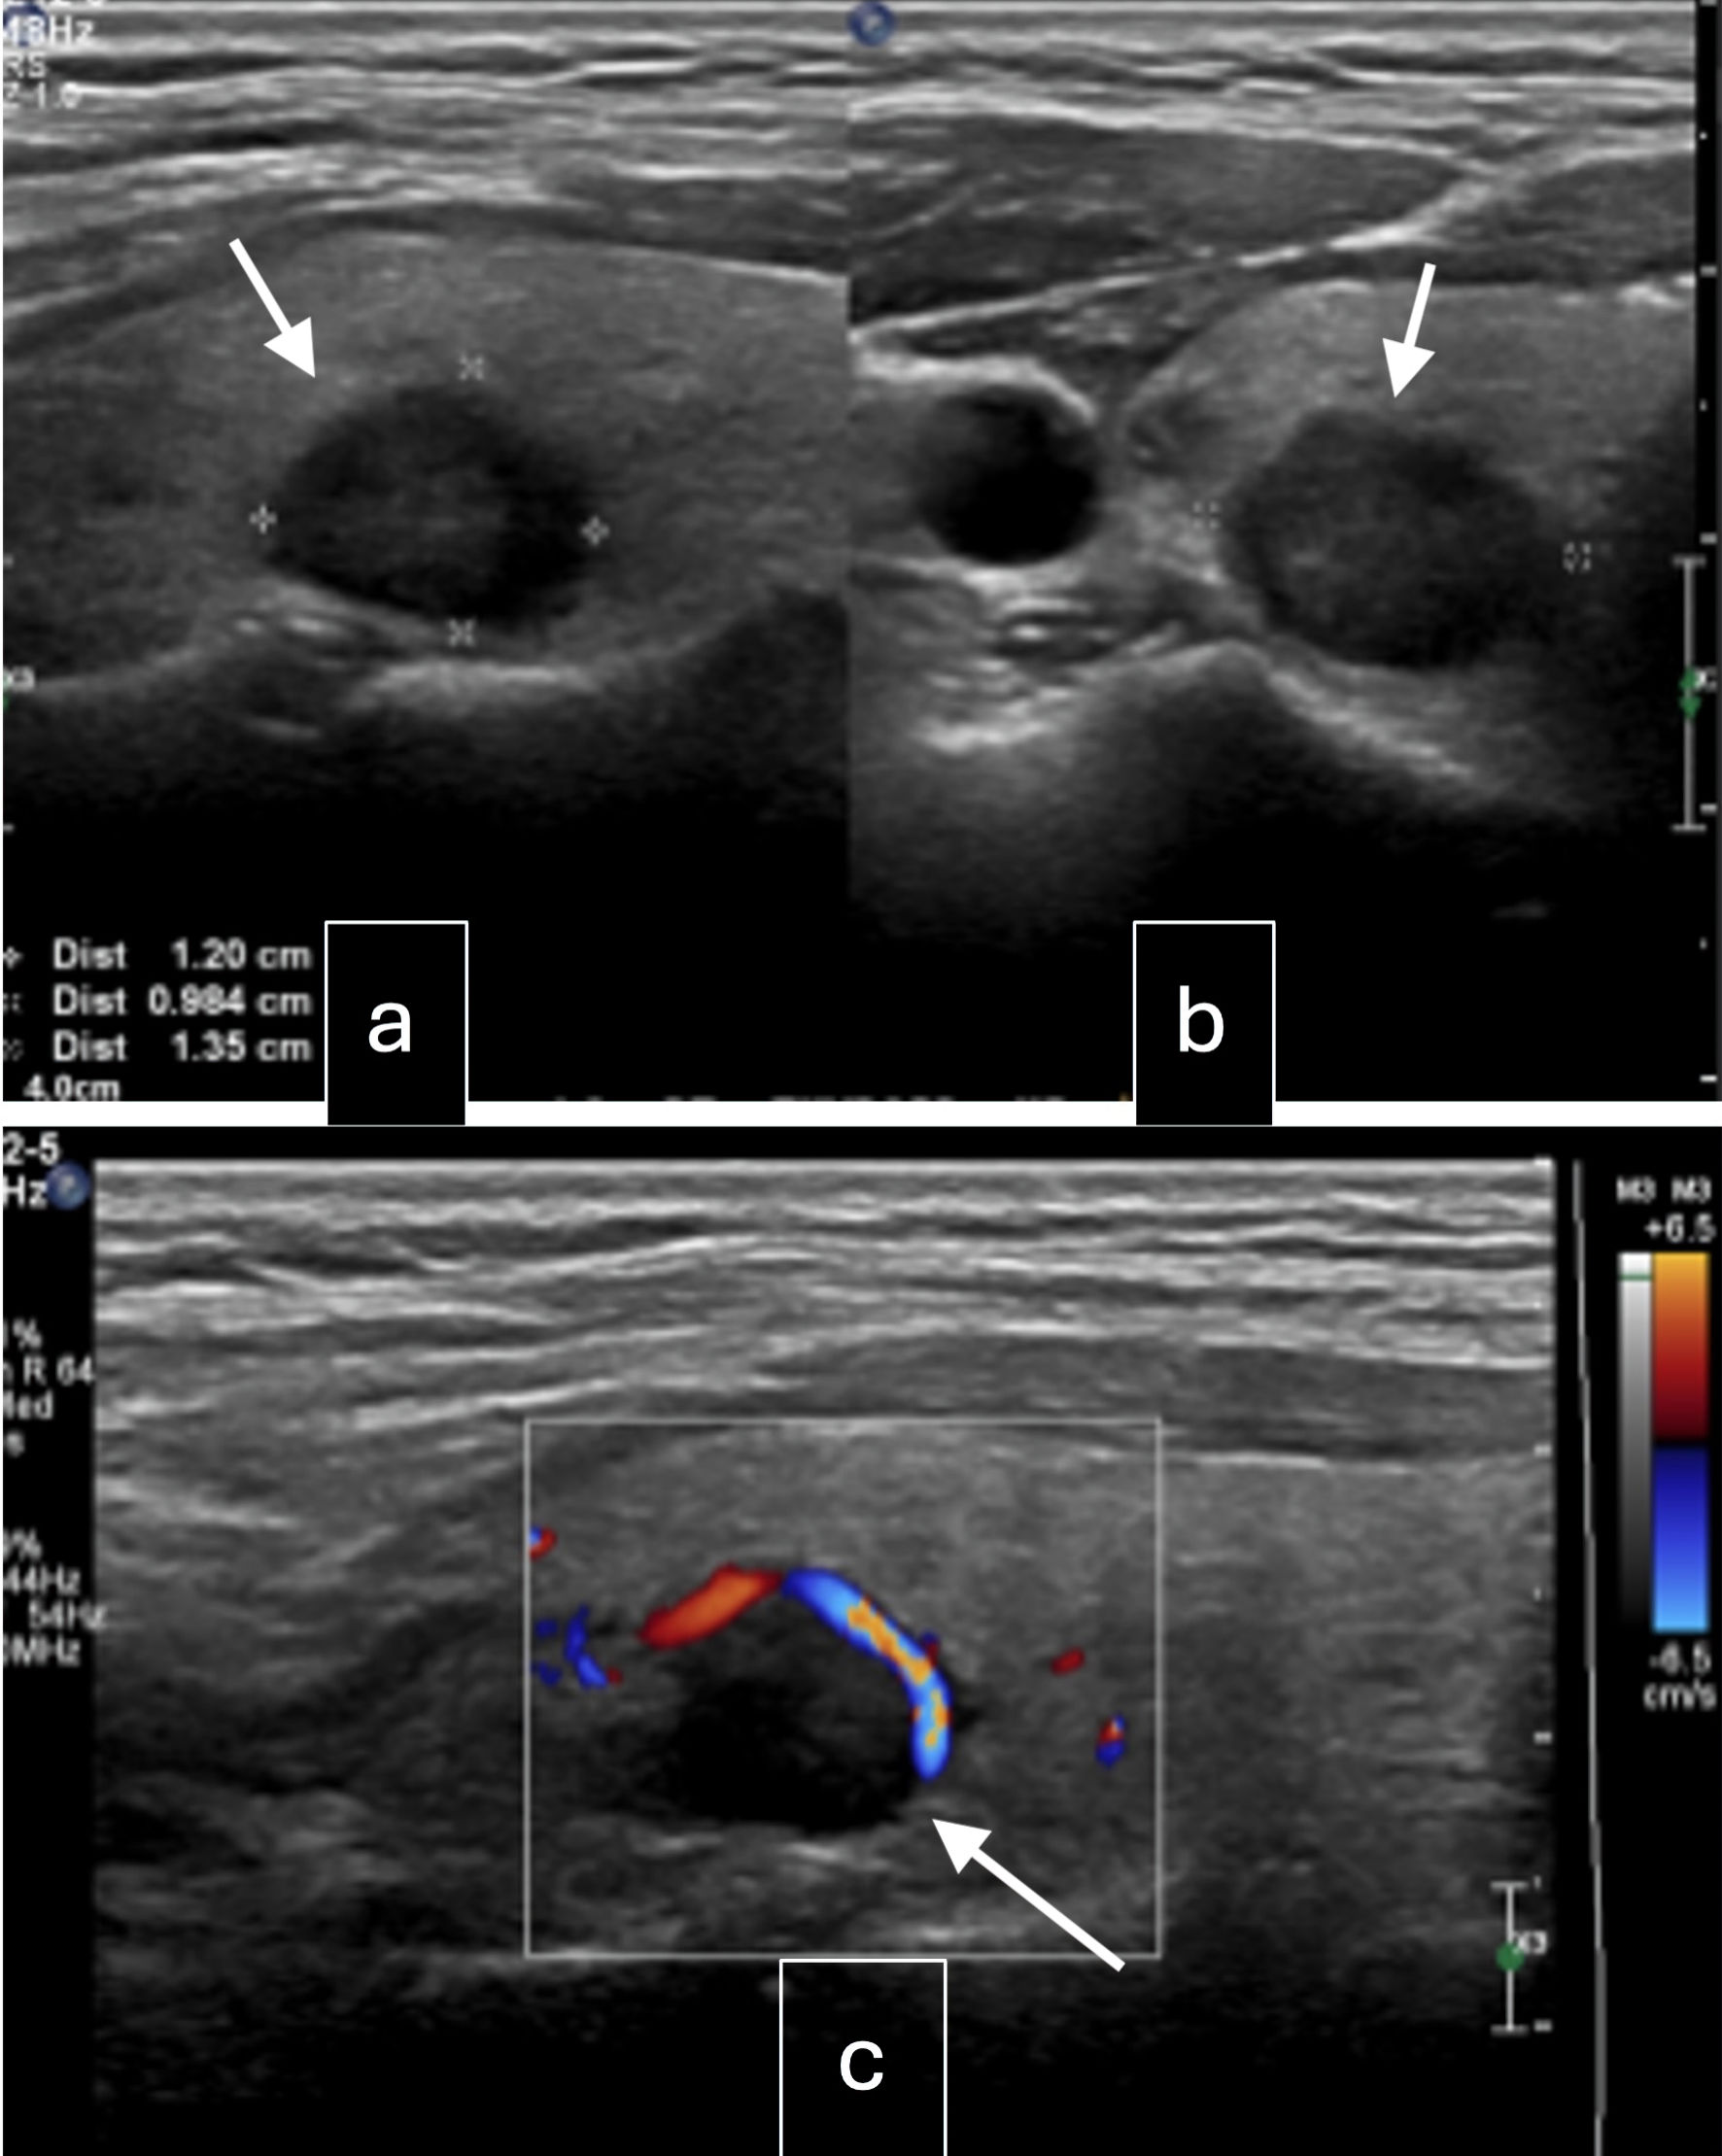

The patient was then referred to our institution for further management. Her case was discussed in a multidisciplinary team meeting. Thyroid function tests were normal, while thyroglobulin (TG) was elevated at 1,066 µg/L. She was referred to ear, nose and throat (ENT) and endocrinology for further assessment of the thyroid nodule. Ultrasound of the thyroid gland (Fig. 1) showed multiple solid thyroid nodules in both lobes, with the dominant nodule in the right middle pole at 1.2 × 1.4 × 1 cm, and a left cervical lymph node of 1.4 × 1.0 × 0.6 cm heterogeneous, with no fatty hilum and no hilar vascularity. A fine-needle aspiration (FNA) of the right thyroid nodule showed a follicular neoplasm with nuclear atypia, with a 25-40% risk of malignancy. The patient was advised to have staged surgeries. Laparotomy, total hysterectomy, bilateral salpingo-oophorectomy (BSO), omentectomy, resection of peritoneal and sigmoid tumor nodules, and nodal debulking were performed. Intraoperatively, the left ovary was enlarged to 10 × 8 cm, while the right ovary was enlarged to 5 × 5 cm. There were multiple tumor nodules on the omentum, serosal surfaces of the rectosigmoid colon, pelvic peritoneum, rectal epiploicae, and anterior peritoneum. Bulky right obturator and right precaval lymph nodes were removed. The liver, small bowel, and appendix appeared normal. There was no residual disease at the end of the surgery. Final histology showed bilateral ovarian struma ovarii (Fig. 2a, b) with tumor deposits on the surface of both ovaries, fallopian tubes, and uterine serosa and multiple nodular tumor deposits of thyroid tissue in the omentum, sigmoid nodule, and pelvic peritoneal nodules. Lymph nodes taken were negative. Given the size of the primary tumors and the presence of tumor deposits in multiple extra-ovarian sites, malignant transformation in struma ovarii with a highly differentiated follicular carcinoma was considered.

Figure 1. Ultrasound of the neck. (a) Right lobe mid pole nodule: well-circumscribed, solid, iso-hypoechoic, wider than tall with peripheral vascularity, 14 × 12 × 10 mm (arrow, intermediate suspicion). (b) Right lobe upper pole nodule: spongiform lesion, 6 × 4 × 3 mm (arrow, low suspicion). (c) Left lobe mid pole nodule: well-defined, solid, hypoechoic lesion with coarse internal calcifications, 7 × 7 × 5 mm (arrow, intermediate suspicion).